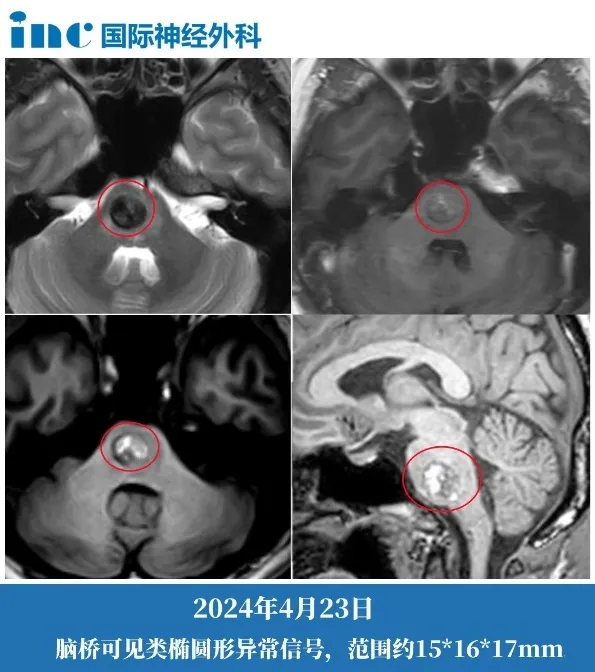

但2024年4月病情突然加剧:肢体乏力导致行走困难,左侧全身麻木感蔓延至面部,复视、耳鸣症状接连出现。复查核磁显示病灶扩大至15×16×17mm,位于生命中枢的"不定时炸弹"正快速恶化。